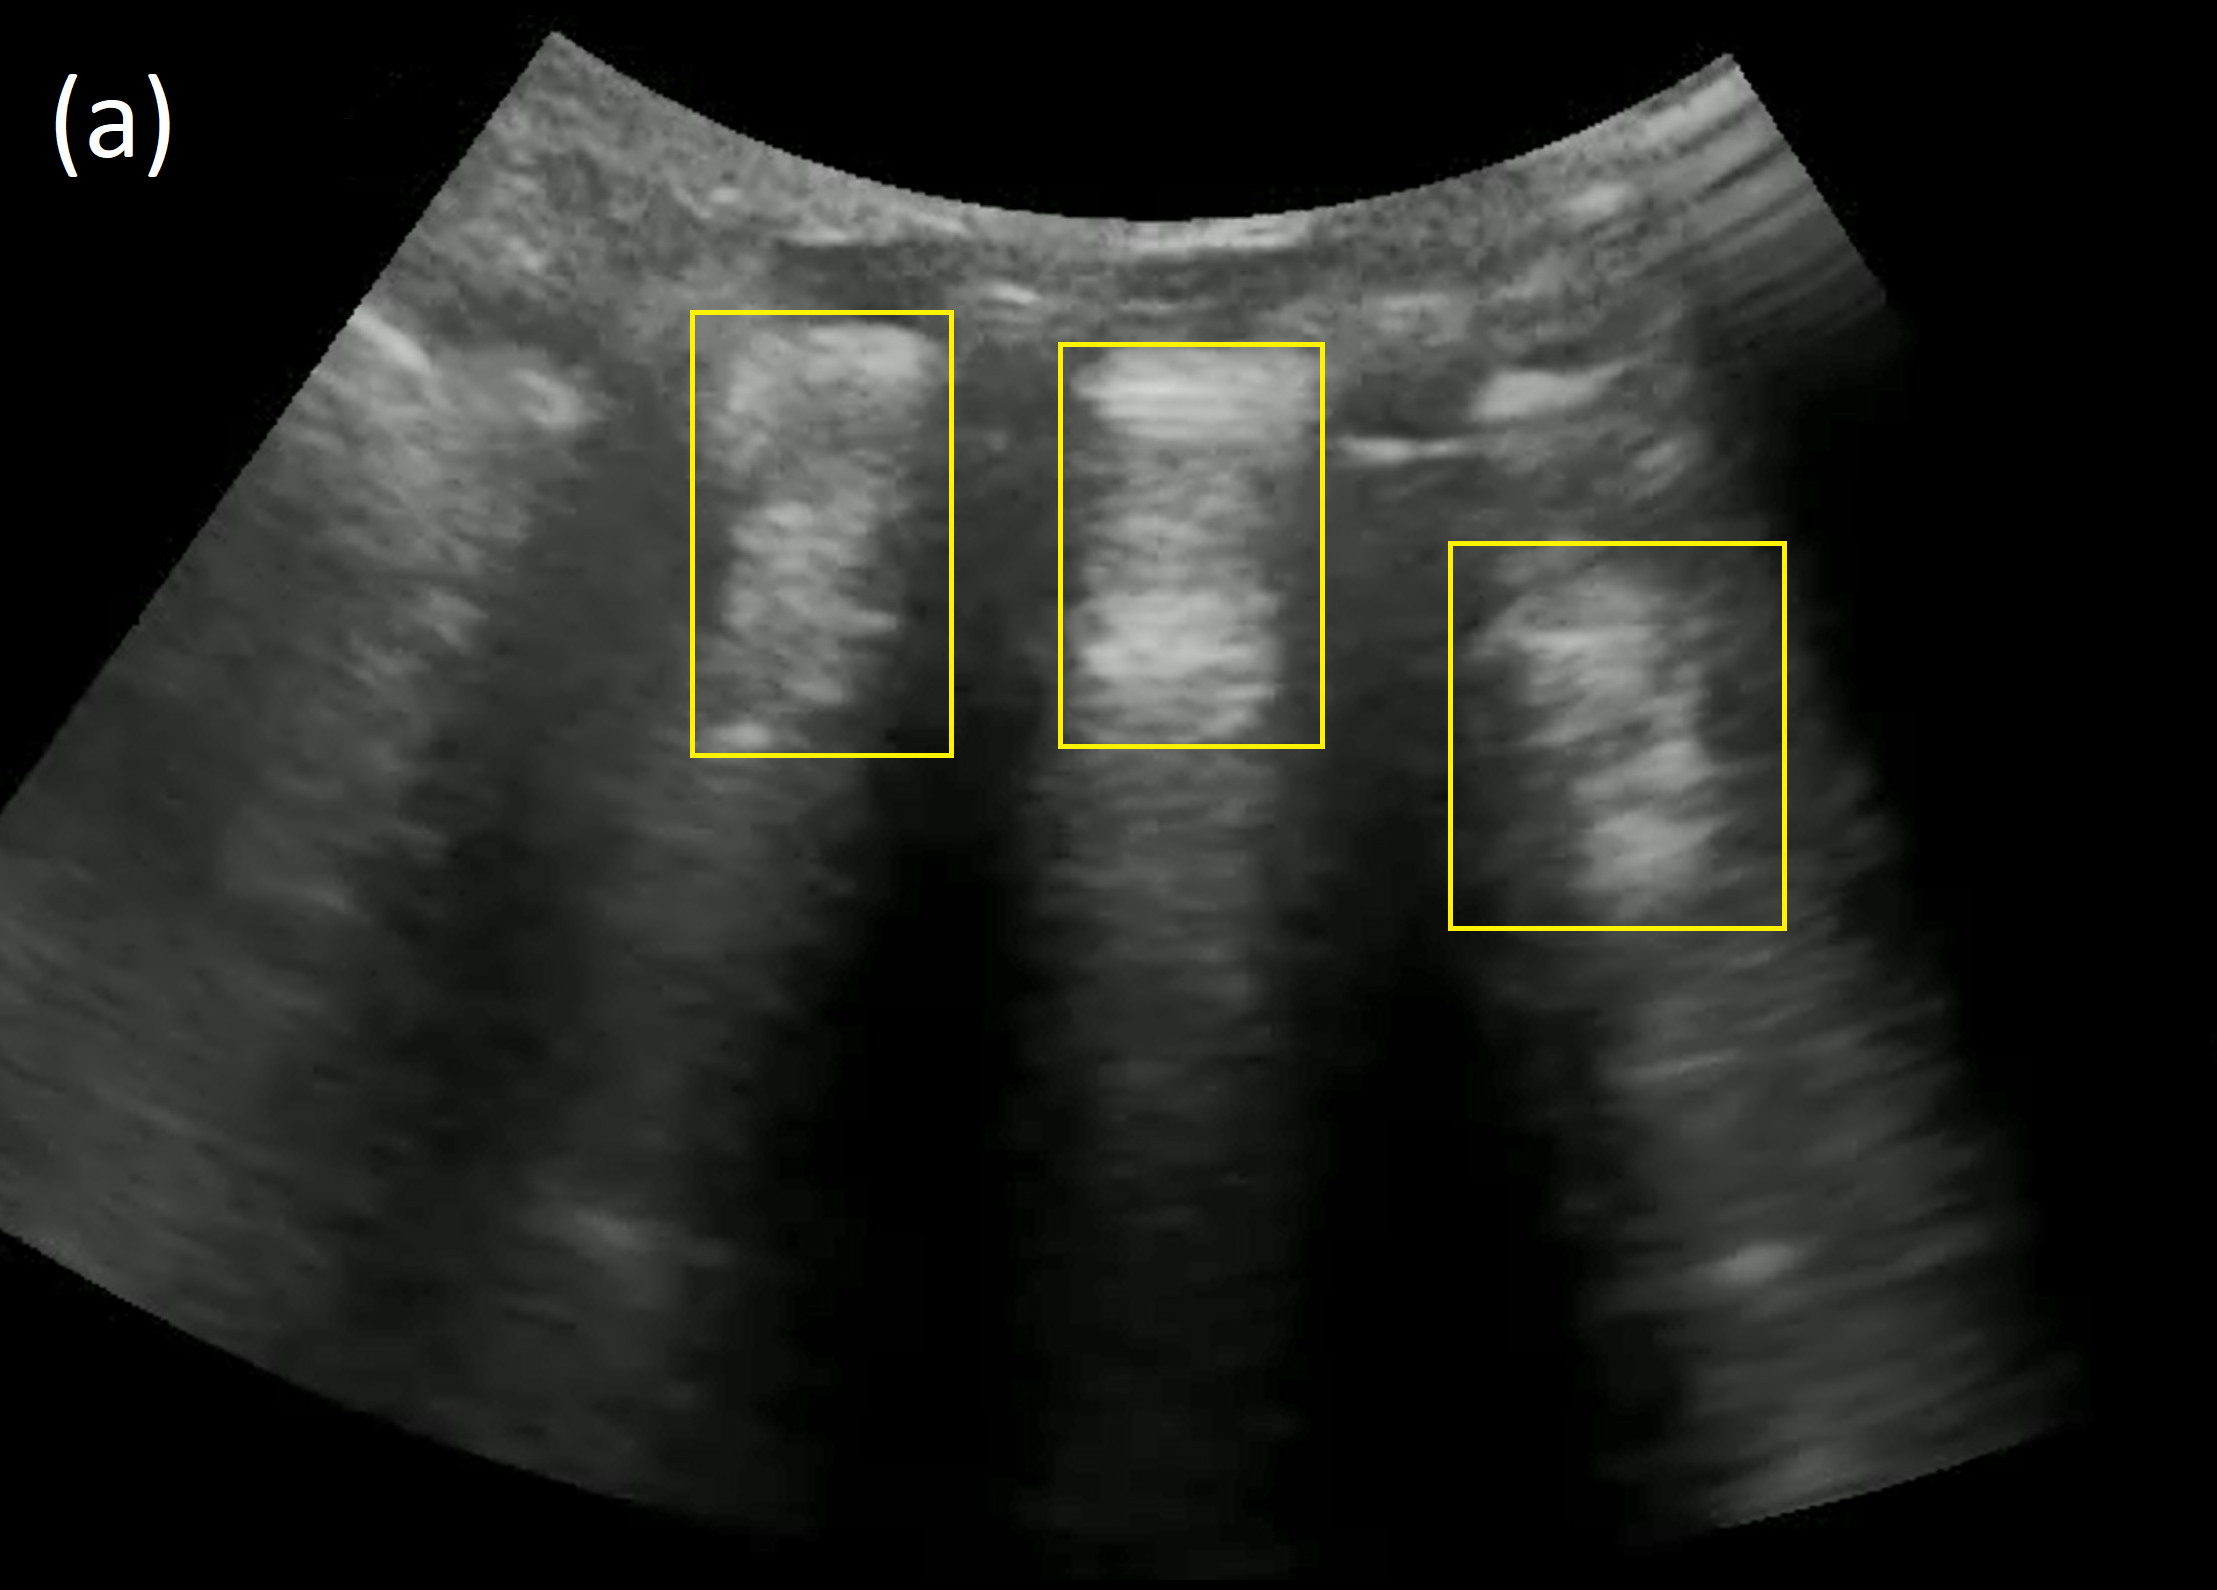

Refer to caption

Figure 1: Consolidation in lung ultrasound. (a) Real consolidation image: infection-induced inflammation causes fluid buildup in the alveoli, presenting as hyper- and hypo-echoic splotches (yellow boxes). (b) Synthetic consolidation image.

Lung ultrasound images largely consist of artifacts generated by acoustic impedance mismatches between lung tissue, fluid, and air. To the trained eye, these artifacts convey information about lung pathologies such as consolidation, which manifests as sub-pleural hyper- and hypo-echoic splotches caused by inflammatory alveolar fluid buildup. See Figure 1. We observe that the synthetic images also display such features and artifacts and preserve the architecture of lung ultrasound images. Figure 3 shows examples of synthetic and real, consolidated and normal, lung ultrasound images. Prominent features of lung ultrasound include the “bat sign” [2] and “rib shadows”, caused by the pleural line and the impenetrability of ribs to ultrasound. These can be observed in the real and synthetic lung images (r1–r4, s1–s4). Pleural lines, A-lines (multiple-echo artifacts of the pleural line) are also present and qualitatively similar in synthetic images (r3, s3). The “shadows” on the left and right sides of images (r1, r2, r4, s1–s4) are caused by poor acoustic contact between the edges of the curvilinear transducer and the child’s body, which is another realistic element of the the synthetic images. Other features of lung ultrasound also appear in synthetic images, such as “hepatization”, caused by excessive fluid accumulation, as seen in (s1, s2). Additional synthetic examples are provided in the supplement.